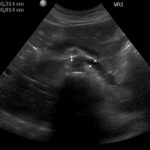

Fig. 3. Examen ecográfico abdominal, se observa compresión de la vena renal izquierda entre la aorta y la arteria mesentérica superior (mide 3,1 mm a nivel del compás y 8,1 mm en el segmento proximal al riñón izquierdo).

Hallazgos imagenológicos. En el eco Doppler ginecológico por vía transvaginal se observa varicocele pelviano (Fig. 1). La vena ovárica derecha mide 3.8 mm, y la izquierda, ectásica, 7.4 mm (Fig. 2). En el eco Doppler abdominal se visualiza la vena renal izquierda, de 3.1 mm en topografía del compás aorto-mesentérico y 8.1 mm en el segmento proximal al riñón izquierdo, con una velocidad 50cm/s en el compas y 30cm/s en el segmento proximal al riñón. El estudio corresponde en primera instancia a un síndrome de Nutcracker (Fig. 3).